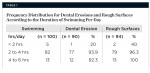

Among the 100 swimmers, 90% had dental erosion (DE) (Figure 1) and 94% had rough surfaces (RS). The prevalence of erosion and rough surfaces was found to be more with increasing duration of swimming per day (Table 1). Those who were regularly swimming for < 2 hours showed 20% DE and 40% RS; those swimming for 2 to 4 hours showed 93.9% DE and 96.3% RS; and those who were swimming for > 4 hours showed 92.3% DE and 100% RS, respectively.